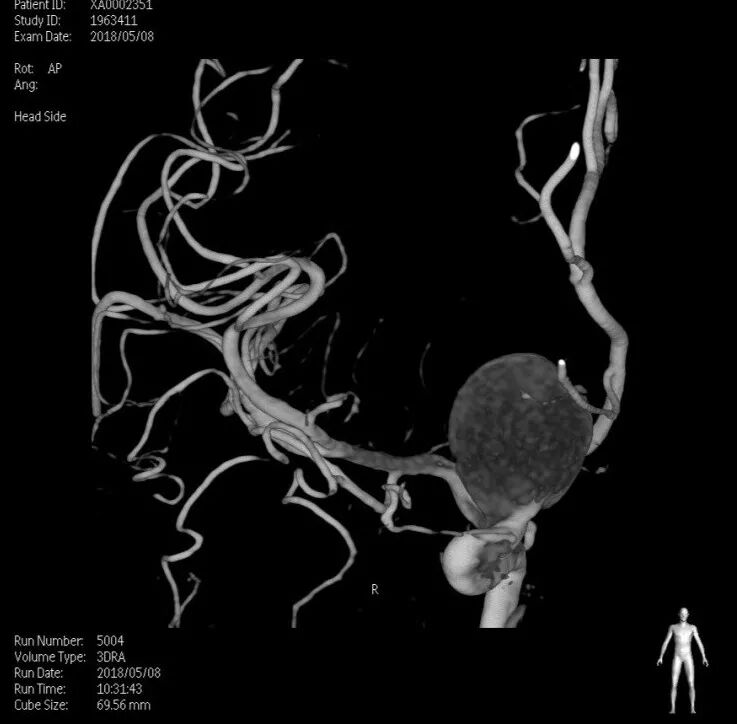

入院后完善DSA检查提示颅内多发动脉瘤:右侧颈内动脉眼段大动脉瘤(约18*19mm,瘤颈6.6mm),左侧眼动脉段及床突段动脉瘤。和家属沟通病情,告知介入和开颅手术风险利弊后,患者家属选择开颅动脉瘤夹闭手术治疗。进一步行DSA+CT融合,模拟手术入路视角。

术前MRA和CTA

右侧眼动脉瘤

左侧眼动脉段及床突段动脉瘤

术前融合后模拟开颅骨窗

术前融合后模拟显微镜视角

结合本病例,我们术前利用复合手术室飞利浦DSA血管机,造影后即刻行CT扫描。由于是在同一机器环境下完成的两种模态扫描,减少了伪影干扰,解剖结构电脑自动吻合,故影像融合精度极高。并且因为是双模态融合,可以用不同颜色标记血管和骨窗,增加了对比度,提高了分辨率,较CTA有明显优势。利用术前融合模拟手术入路,放大后观察发现动脉瘤体巨大,紧贴颅底和床突,缺乏至少2mm的近端阻断空间,术中需要磨除前床突。但术中发现动脉瘤表面张力极高,紧贴床突硬脑膜,高速磨钻操作存在巨大风险。而术中球囊阻断颈内动脉后,动脉瘤张力明显下降,依靠吸引器轻轻牵拉即可暴露出瘤颈,不必要磨除床突,降低了手术复杂度。